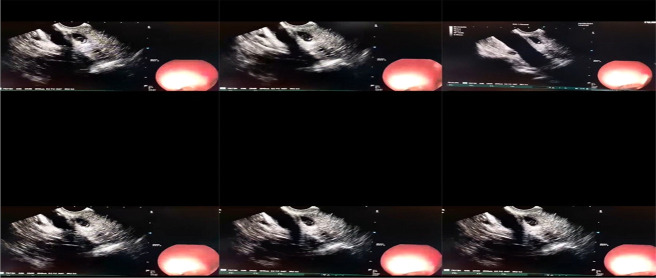

This article discusses Fasciola hepatica infection, a zoonotic parasite that lives in the liver bile ducts. A 31-year-old female patient was diagnosed with symptoms such as nausea, increased liver enzymes, and right upper quadrant pain for about a year. The parasite was detected in the common bile duct by Endoscopic Ultrasound (EUS) and removed by Endoscopic Retrograde Cholangio Pancreatography (ERCP). Treatment was performed with 10 mg/kg triclabendazole. Eosinophilia, abdominal pain, and dietary history are important clues in the diagnosis of infection. Imaging methods, especially EUS, play a critical role in diagnosis. With this method, parasites can be seen as mobile hyperechogenic structures. If untreated, parasites can survive in their hosts for many years, therefore early diagnosis and treatment are important in preventing complications. It is recommended to monitor the eosinophil levels and serological test results of patients after treatment. As a result, EUS is a very valuable diagnostic tool in suspected cases.

Abstract Image